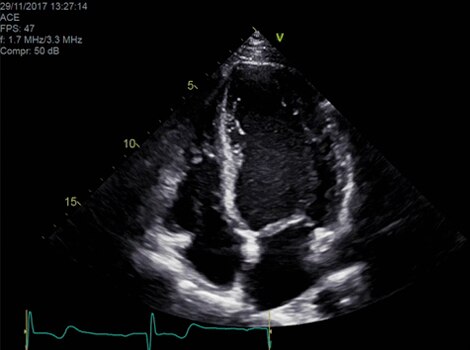

Vivid Portfolio

Cardiac Auto Doppler automatically provides Doppler measurement results for the most common parameters, with minimal user guidance.  Read More

Vivid E95

cSound beamforming technology for exceptional visualization quality with impressive resolution in 2D, color flow, Doppler and 4D formats. Read More

VividTM Family Cardiac Ultrasound Automated Function Imaging (AFI)

Assess left ventricular function and cardiac performance with clarity, improving clinical confidence.  Read More

Vivid Family Cardiac Ultrasound

Vivid E95 with cSound performance makes 4D as easy as 2D to quantify left ventricular wall motion. Read More

Due to the high mortality rates by the time patients are symptomatic, it is important to identify patients at risk, even when they are asymptomatic. Echocardiography can identify issues or abnormalities related to Aortic Valve structure and function.3

Automated Ejection Fraction and LV wall motion quantification. Read More

Semi-automated 3D valve assessment. Read More

Provides Doppler measurement results for the most common parameters, with minimal guidance. Read More

Vivid Family Cardiac Ultrasound with Auto EF